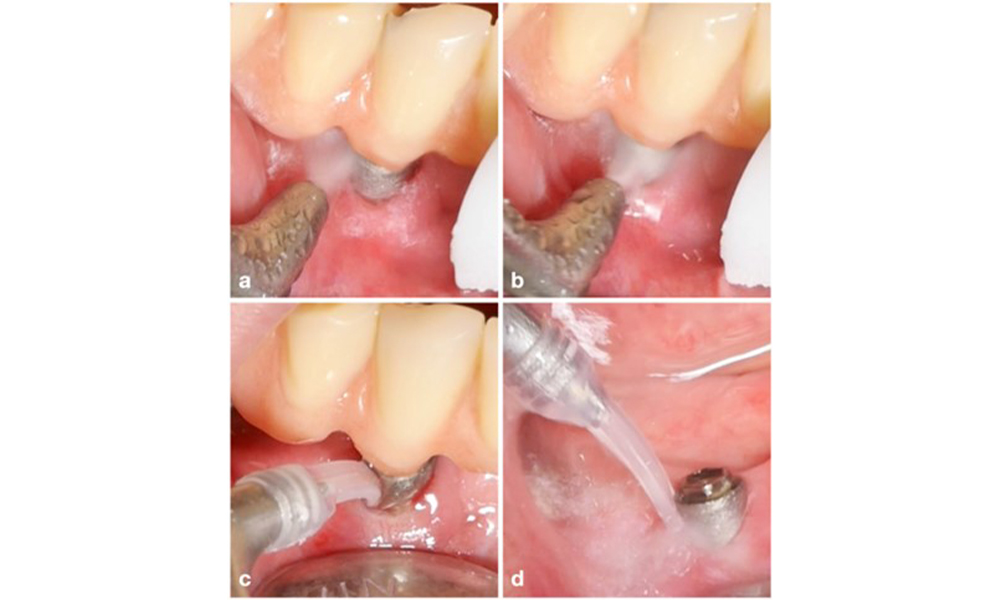

Implant in position 26 with peri-implant mucositis (a–c). The probing depth value of 5 mm (b) remains consistent with the measurement taken a few weeks after placing the prosthetic reconstruction. There is bleeding on probing (c) but the radiograph indicates no additional bone loss beyond what is expected for marginal bone remodelling (d).

Figure 1. Implant in position 26 with peri-implant mucositis (a–c). The probing depth value of 5 mm (b) remains consistent with the measurement taken a few weeks after placing the prosthetic reconstruction. There is bleeding on probing (c) but the radiograph indicates no additional bone loss beyond what is expected for marginal bone remodelling (d).